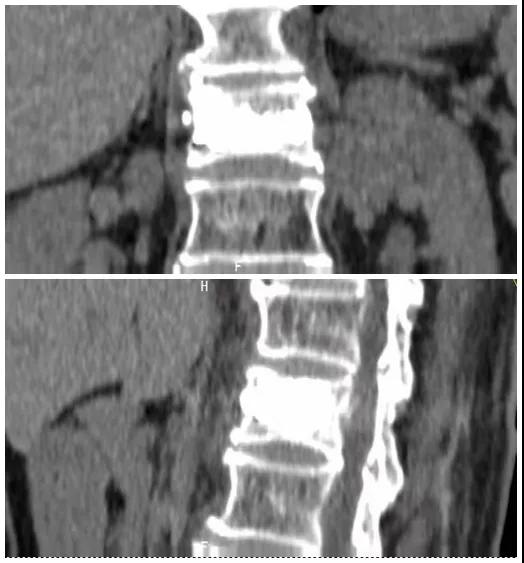

術(shù)后復(fù)查CT可見骨水泥彌散充分